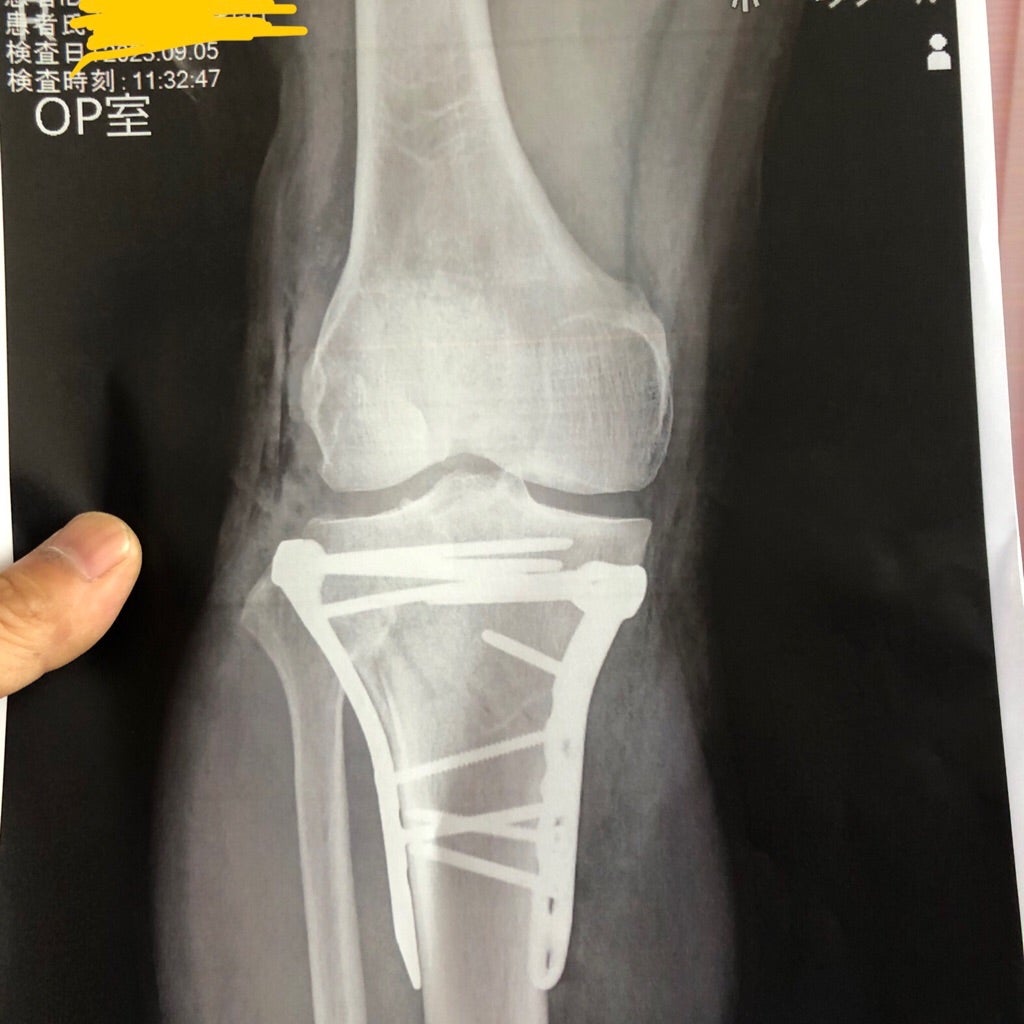

先月、4日にトラックから転落し骨折する事故に見舞われ現在、復帰に向けてリハビリ中。

まさか、脛骨腓骨とも折れてるとは思わ無かった(笑